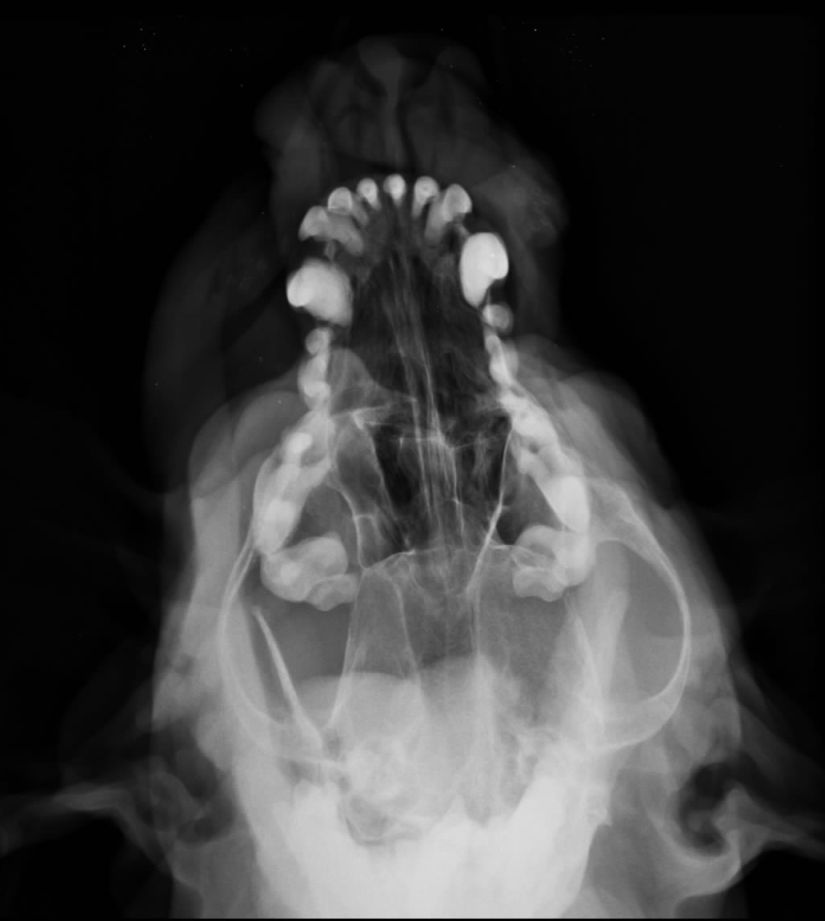

Esta herramienta diagnóstica es de suma importancia, ya que a través de sombras de diferentes tonos podemos ver los contornos de diferentes órganos. Entre otra cosas, es muy útil en en la evaluación del tórax, permite diferenciar los detalles de los pulmones, pleura, corazón, etc. Igualmente a nivel de la columna y otras articulaciones, como es el caso de la cadera (art. coxofemoral), podemos definir lesiones crónicas, lesiones congénitas y considerar un tratamiento. Especial utilidad cuando existen fracturas, según su comportamiento y extensión se definirán los métodos de reducción mas adecuados.

Radiografías simples

Radiografia digital simple y con contraste